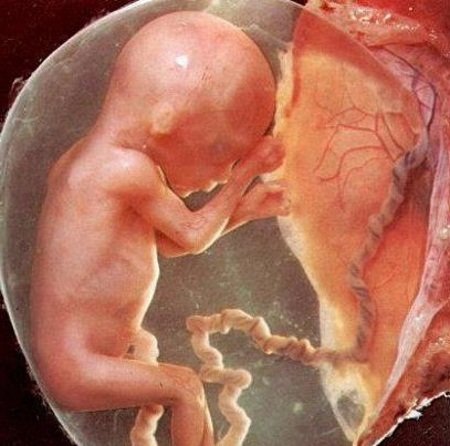

Фото: UGC21 неделя беременности — это полноценный старт эндокринной системы ребенка. Рост и развитие малыша в дальнейшем будут происходить очень быстро. Организму мамы придется реагировать на эти изменения и приспосабливаться к ним. Узнайте, с какими трудностями столкнется беременная на 21-й неделе, какие изменения произойдут с

Представление о том, какие физиологические изменения принесла малышу 21 неделя беременности, даст фото, сделанное узи-специалистом во время планового обследования.

Фото: pixabay.com: UGCСелезенка плода активно вырабатывает лейкоциты и эритроциты. На этом этапе доктора определят его группу крови и резус-фактор. Эти показатели будут очень важны в будущем, поскольку покажут, нет ли конфликта с резусом и группой крови матери.

21 неделя беременности на УЗИ, которое является плановым, покажет не только новые размеры плода, но и его предлежание, развитие органов, пол. Кроме того, доктора могут оценить состояние плаценты, пуповины, количество околоплодных вод. Все это показатели того, как протекает беременность, нет ли угрозы ранних родов.